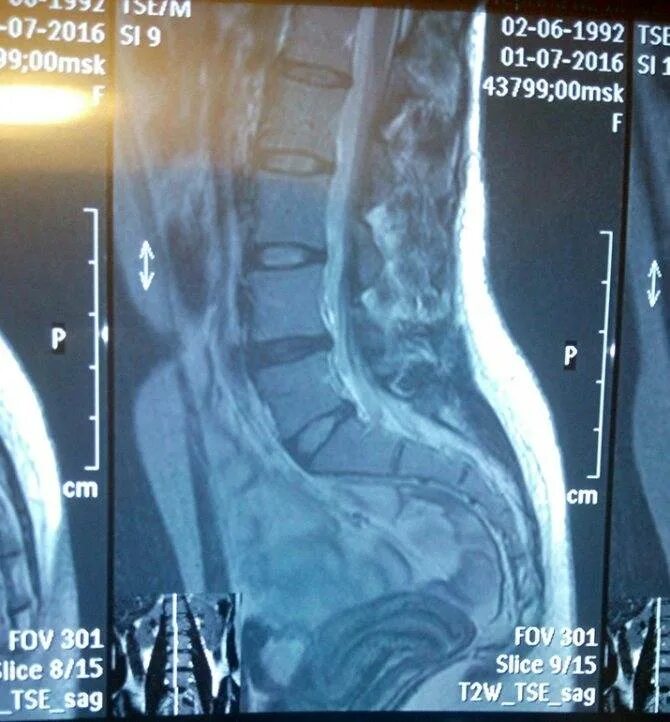

Можно ли забеременеть при загибе матки